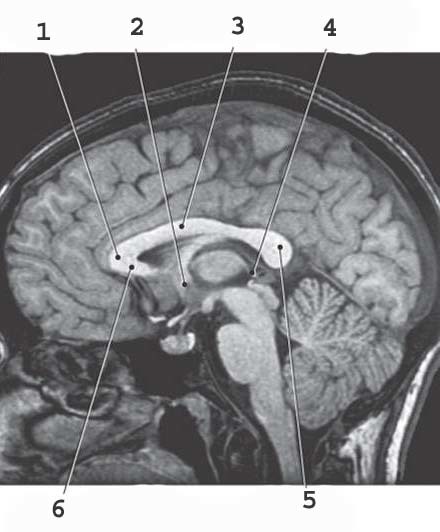

1

Midbrain

Thalamus

3

Pineal gland

6

cerbral aqueduct

12

infundibulum

13

mammilary body

14

optic nerve

15

hypothalamus